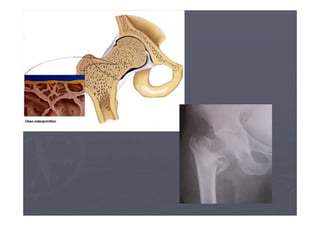

►As fraturas por osteoporose mais freqüentes

são as de quadril, coluna e punho.

► Por meio de métodos radiológicos convencionais, a

osteoporose só é detectada quando já houve

perda de 20% a 30% da massa óssea.